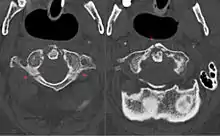

كسور الفقرات العنقية

- كسر جيفرسون.[3]

- خلع فهقي محوري (بالانجليزية: Atlanto-axial subluxation)

- كسر هانغمان (بالانجليزية: Hangman's fracture)

- كسر الفائق (الناتئ السني) للمحور.

- مفصل وجيهي قافز (أحادي أو ثنائي الجانب)

- كسور الفقرات العنقية غير المحورية.

- الكسور القلعية.

- كسر الدمعة.